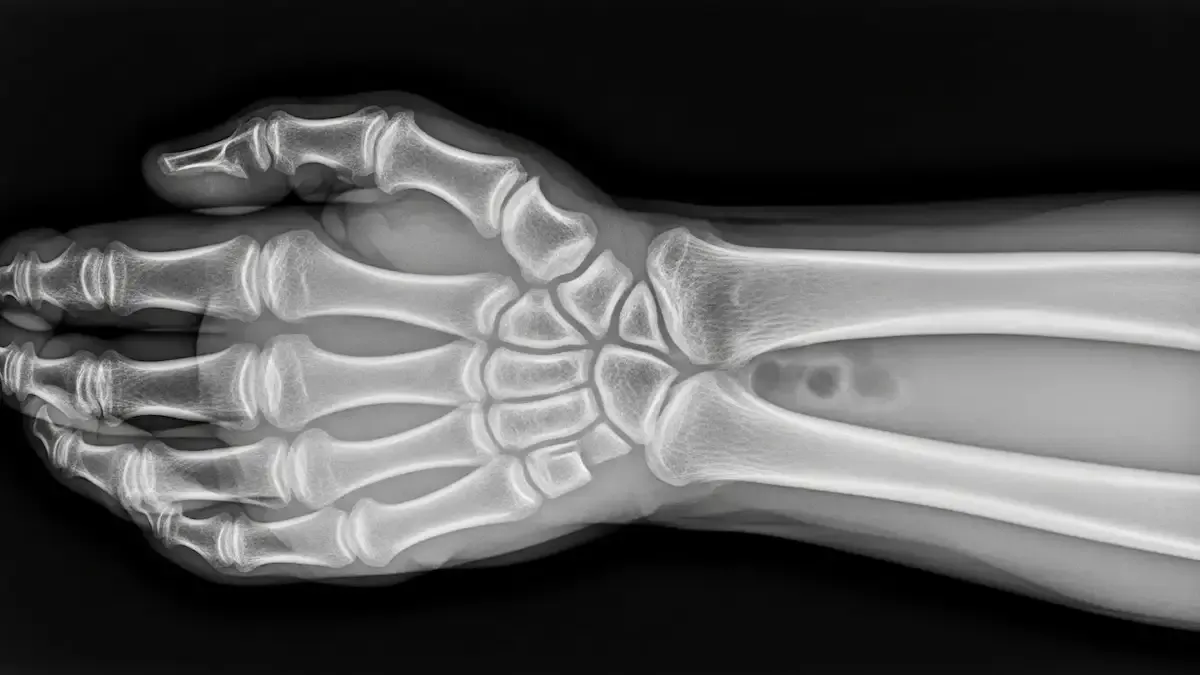

A artrose do punho ocorre pelo desgaste progressivo da cartilagem que reveste as articulações da região, como as articulações radiocárpicas, ulnocárpicas e intracárpicas.

O diagnóstico da artrose do punho parte da avaliação clínica, considerando queixas de dor, sensação de rigidez e redução da mobilidade articular.

Exames de imagem, como radiografia, confirmam o desgaste articular, enquanto a ressonância magnética pode ser solicitada para avaliar cartilagem, ligamentos e estruturas associadas.

Na maioria dos casos, a radiografia identifica o desgaste articular e a presença de osteófitos.